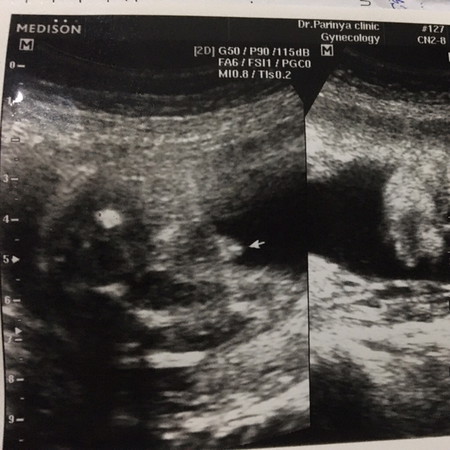

ให้แม่ๆทาย ว่าแบบนี้ ญ รึ ช ค่ะ

ชายนะคะ แม่ซาวตอนกี่วีคคะ เรากำลังจะซาวด์ดูเพศสัปดาห์หน้าแต่ไม่รู้จะเห็นไหม

น่าจะชายนะคะ เพราะมีโผล่ออกมา ถ้าของผู้หญิงจะไม่โผล่

น่าจะผู้ชาย คะเเม่ มีจู๋โผล่มาด้วย

หน้าจะชายจ้า หน่อไม้แหลมเชียว

ไม่ต้องทายเลยค่ะเเม่ แมนมาเลย

ชายคะ แม่ซาวด์ตอนกี่สัปดาห์คะ

25 สัปดาห์ค่ะ

แหลมมาขนาดนี้น่ะแม่ 555

ชายจ้า แหลมมาเลย😆